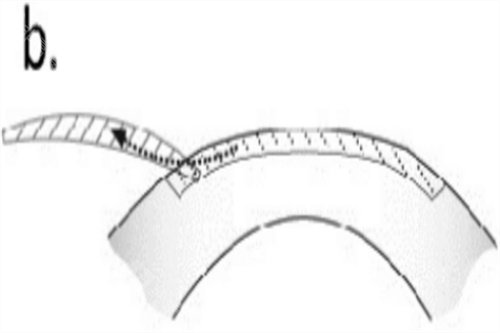

2、半飞秒激光手术

技术特点:保留角膜瓣,改善较快